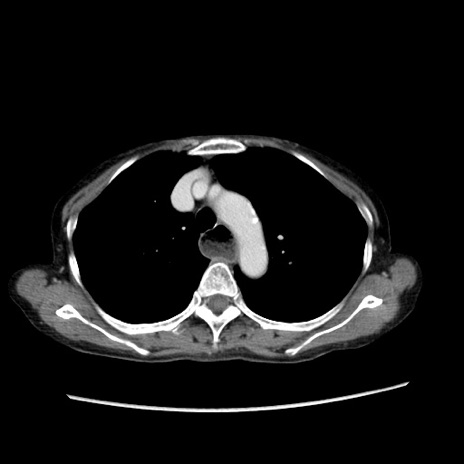

症例25(横断像)

【症例】80歳代女性

【主訴】胸のつかえ感

【現病歴】約9時間前に食後から胸のつかえた感じあり、嘔吐あり、来院。

【既往歴】胃癌(全摘)、胆摘、虫垂炎

【身体所見】心窩部に圧痛あり、反跳痛なし。

【データ】WBC 5700、CRP 0.05